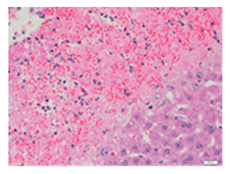

Liver wet weights of all rat groups showed no significant differences (Table 8). According to histochemical hematoxylin and eosin (H&E) staining, treatment with the highest dose of MPE (1000 mg/kg BW) did not result in morphological changes in the liver tissue (B) when compared with DI water treatment (A). Obviously, CCl4 induction (ip)/DI water treatment (po) caused hepatoxicity, which was indicated by a severe degree of fatty changes and fatty cysts in the liver tissue (C), whereas pretreatments of silymarin (100 mg/kg BW, po) effectively decreased the degree of fatty changes and fatty cysts in the liver when compared with the CCl4/DI water group. Indeed, MPE (250 and 1000 mg/kg BW, po) lowered the degree of lipid accumulation in the liver; inversely, MPE (500 mg/kg BW, po) exhibited a severe degree of lipid accumulation. Apparently, taking paracetamol (2 g/kg BW) induced a severe degree of hepatic necrosis when compared with rats that had not received the treatment. Similarly, pretreatments of silymarin (100 mg/kg BW, po) and MPE (250 and 1000 mg/kg BW, po) revealed a mild degree of hepatic necrosis, while MPE (500 mg/kg BW, po) revealed a moderate to severe degree of hepatic necrosis. Accordingly, the findings imply that the consumption of MPE (1000 mg/kg BW) was not harmful to the liver of healthy rats, while MPE (250 mg/kg BW) did improve fat deposition in the livers of CCl4-fed rats and offered protection against liver cell damage in paracetamol-fed rats.

Wet weight values (mean ± SD) and H&E staining of liver from rats with hepatotoxicity induced by CCl4 and paracetamol.

Each liver was embedded in a paraffin block, cut into slides, deparaffinized, and stained with hematoxylin and eosin (H&E) dye. The liver tissue sections were examined in terms of their histopathological status and photographed under light microscopy by a qualified expert clinical pathologist at the Department of Pathology, Faculty of Medicine, Chiang Mai University, Thailand.